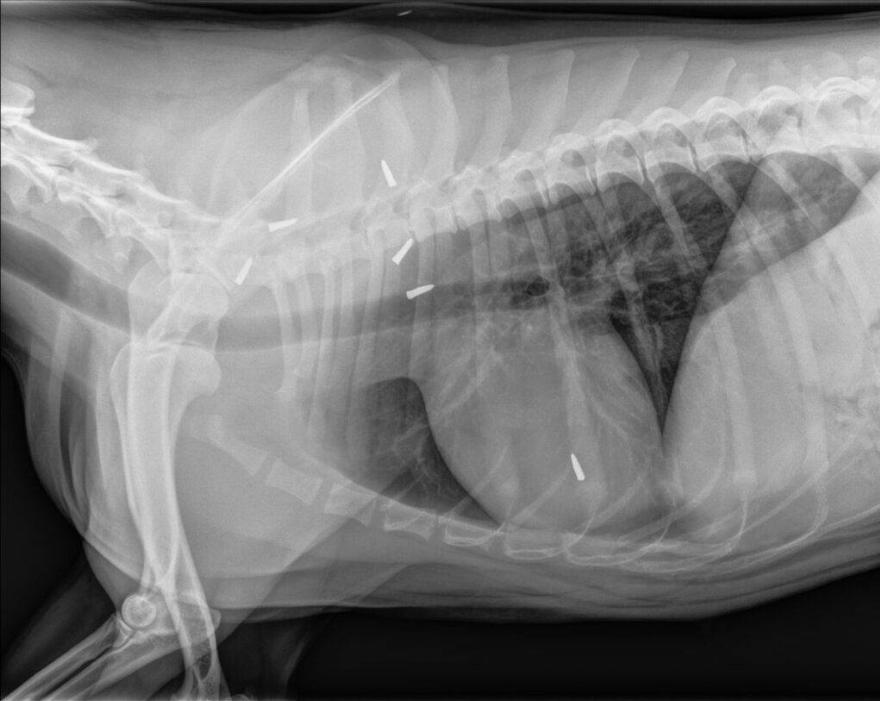

Ευτυχώς, κάποιος κάλεσε την αστυνομία και από εκεί μεταφέρθηκε εσπευσμένα σε κτηνίατρο έκτακτης ανάγκης. Η σφαίρα την είχε χτυπήσει στην περιοχή του λαιμού/του ώμου και είχε σπάσει μερικά από τα πλευρά της, προκαλώντας βλάβη στους πνεύμονες.

Υπάρχουν ακόμα κομμάτια της σφαίρας στον ώμο της, αλλά ο κτηνίατρός της δεν αναμένει ότι αυτό θα προκαλέσει μακροπρόθεσμα προβλήματα υγείας.